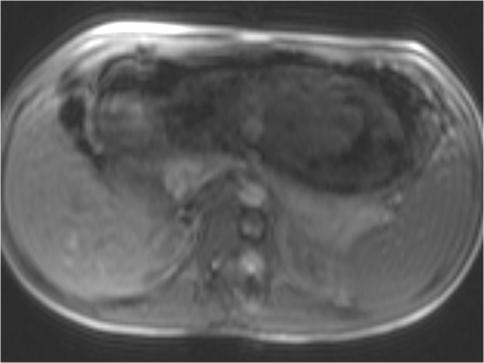

Trichobezoars (hair ball) are usually located in the stomach, but may extend through the pylorus into the duodenum and small bowel (Rapunzel syndrome). They are almost always associated with trichotillomania and trichophagia or other psychiatric disorders. In the literature several treatment options are proposed, including removal by conventional laparotomy, laparoscopy and endoscopy. We present our experience with four patients and provide a review of the recent literature. According to our experience and in line with the published results, conventional laparotomy is still the treatment of choice. In addition, psychiatric consultation is necessary to prevent relapses.

毛发石(毛球)通常位于胃内,但可能通过幽门延伸至十二指肠和小肠(长发公主综合征)。它们几乎总是与拔毛癖和食毛症或其他精神障碍相关。文献中提出了几种治疗选择,包括传统剖腹手术、腹腔镜手术和内镜检查。我们介绍了我们对四名患者的治疗经验,并对近期文献进行了综述。根据我们的经验并与已发表的结果一致,传统剖腹手术仍是首选治疗方法。此外,需要精神科会诊以防止复发。